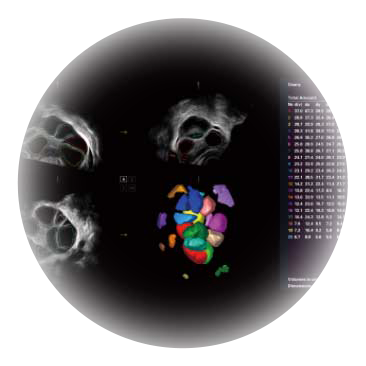

• AVC Follice卵泡自动测量

卵泡结构的自动识别和测量,可显示多组测量数据。